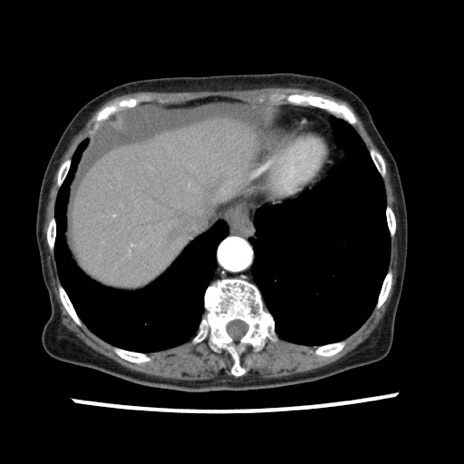

冠状断像

【症例】80歳代女性

【主訴】腹痛

【現病歴】8時間前から腹痛あり来院。

【既往歴】糖尿病、脂質異常症、子宮体癌にて子宮全摘術

【身体所見】意識清明・会話良好だが腹痛で苦悶様、全腹部にわたって反跳痛と圧痛あり

【データ】WBC 13600、CRP 0.14、LDH 224、CK 90